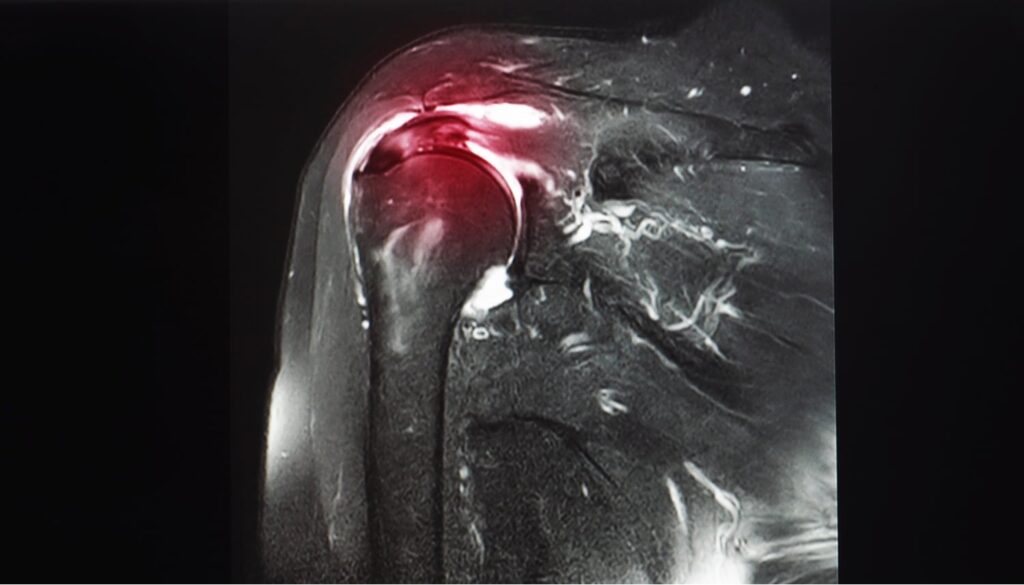

The next day, however, he could barely move due to his shoulder and back pain. He went to the doctor and, after extensive testing, learned that he had partially torn his infraspinatus tendon and suffered other soft tissue injuries.

Over the following weeks and months, nothing seemed to relieve John’s pain. Injections and painkillers helped dull the pain in his shoulder but would quickly wear off. Physical therapy wasn’t effective and only made his symptoms worse. Eventually, he underwent shoulder surgery, but he still struggled with chronic pain.